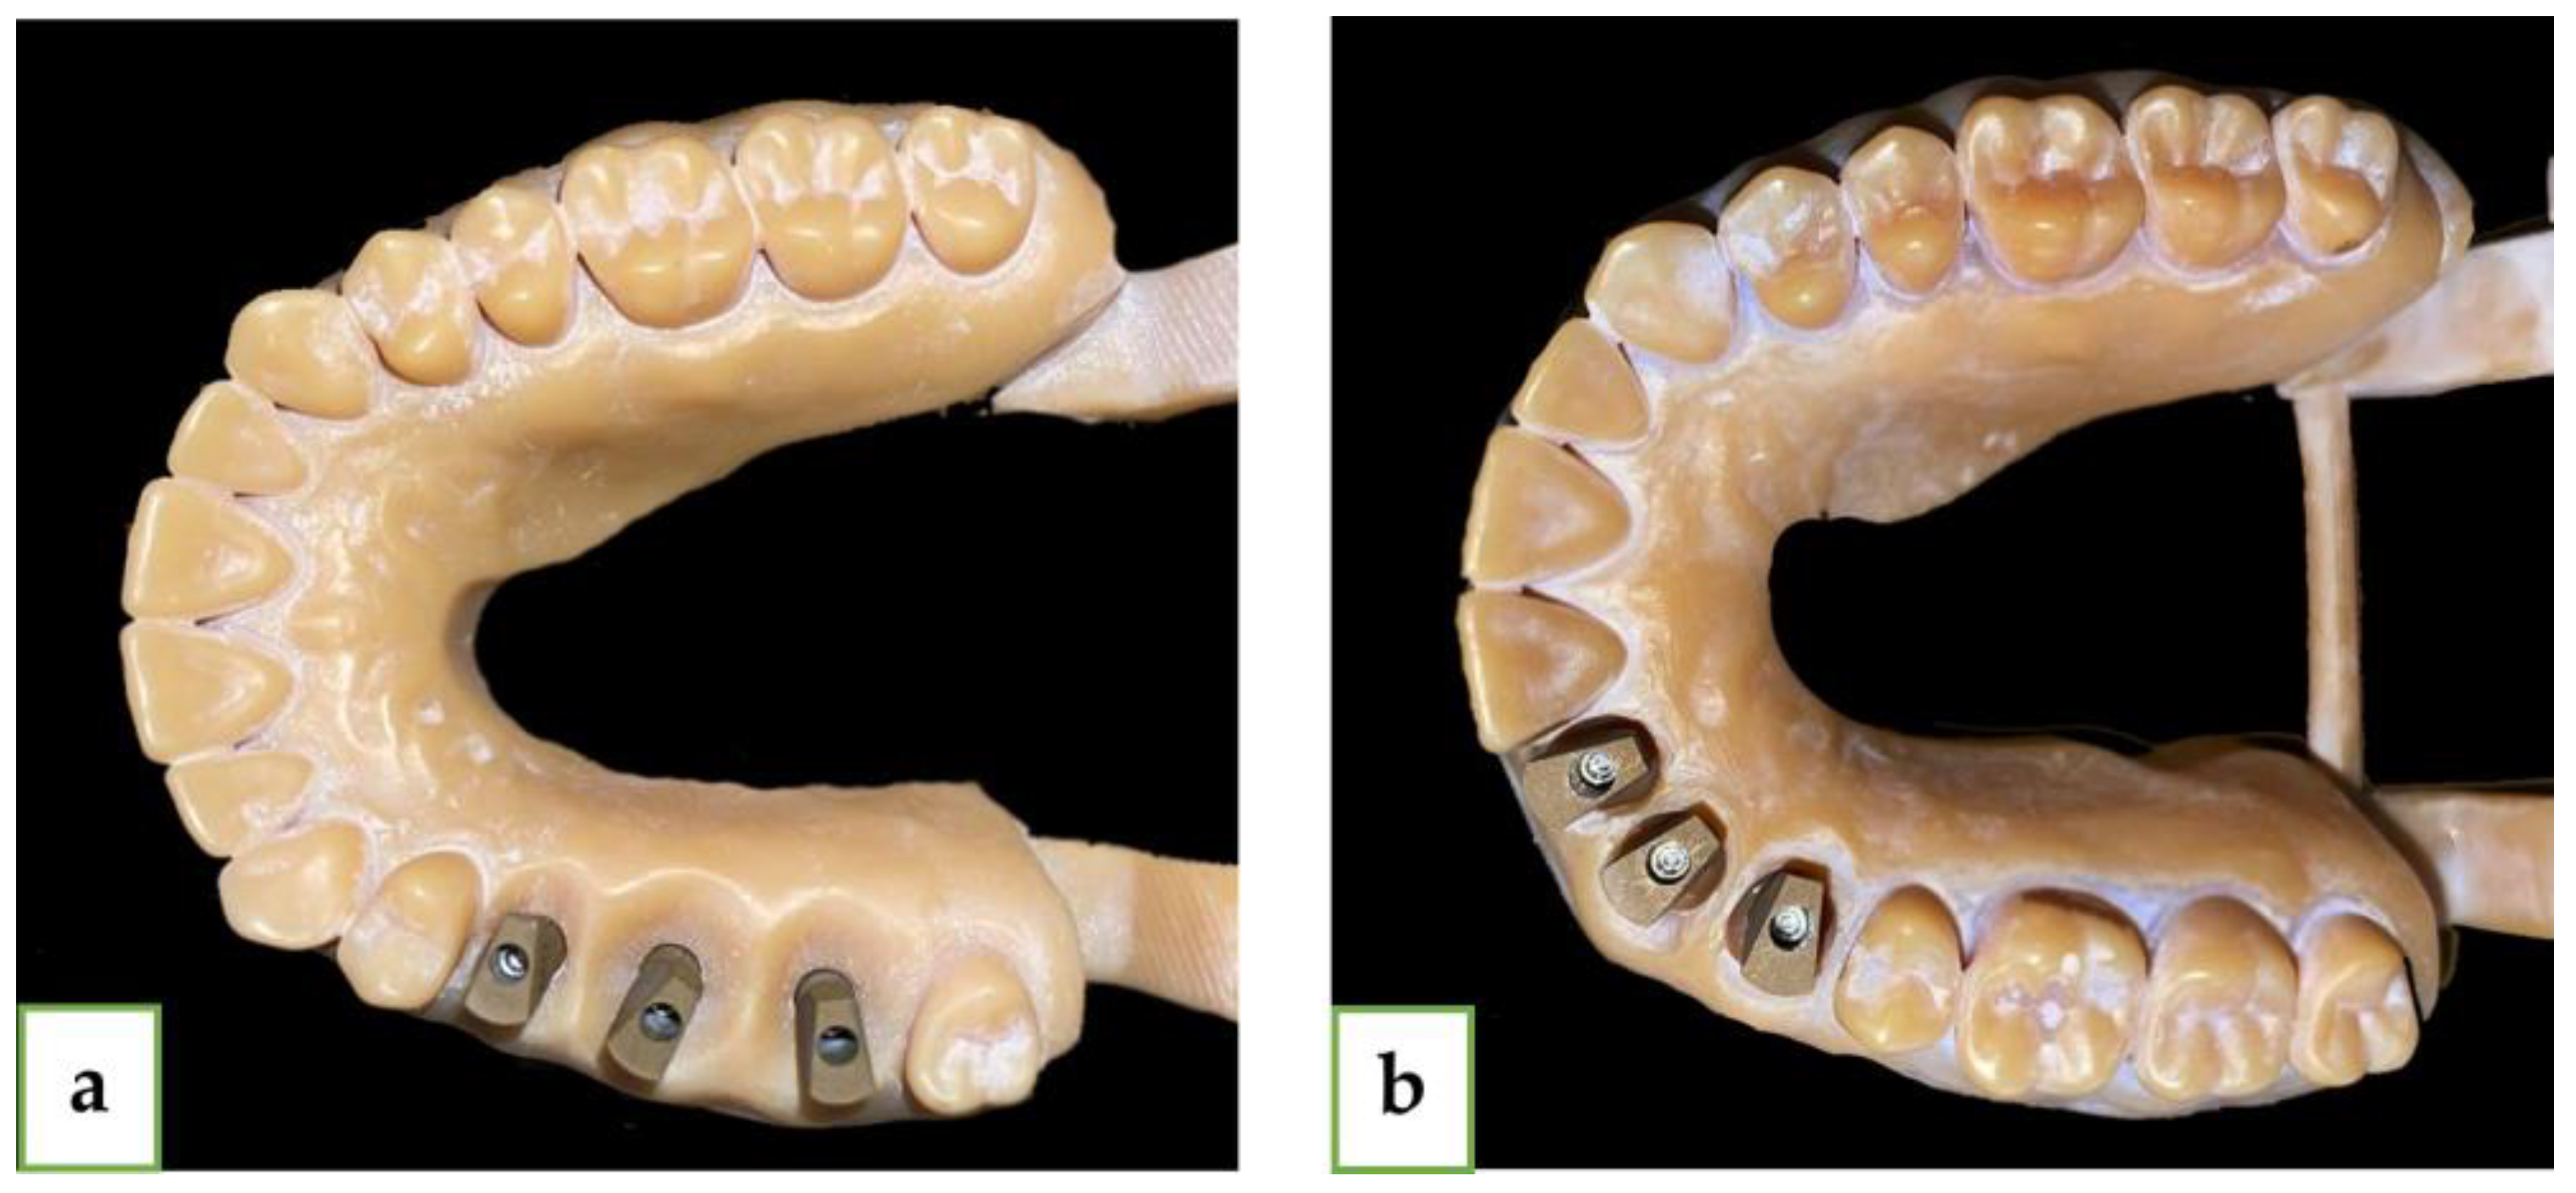

2. Materials and Methods